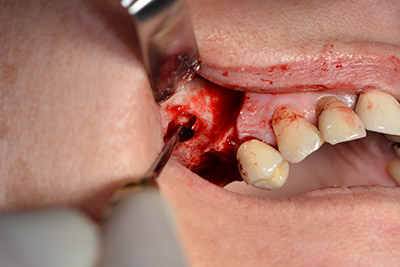

The 59-year-old patient presented with an advanced case of periodontitis, describing an unpleasant feeling and poor taste from the first quadrant in a distal direction. The clinical examination revealed generally enlarged periodontal pockets and very advanced bone atrophy in regions 16 and 14. The radiology confirmed the findings (Fig. 1). Teeth 16 and 14 could not be retained.

Image 1: Orthopantomogram with bone atrophy in region 16–14. *